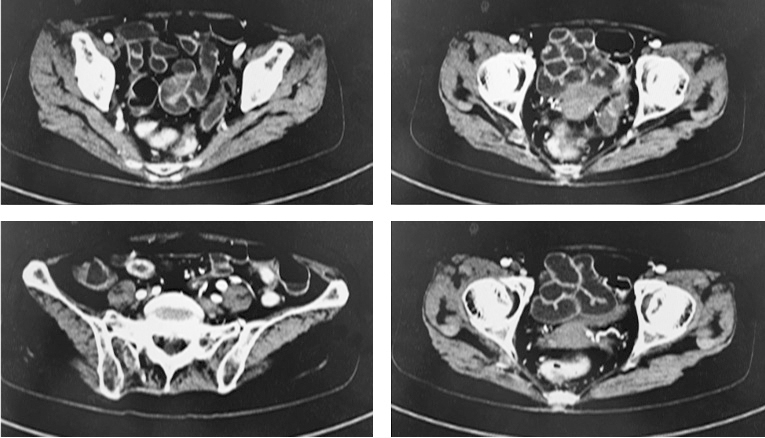

(5)全腹部增强CT:胆囊结石、肝脏、胰腺、脾脏等均未见明显异常,小肠多发节段性黏膜增厚、回盲部及直肠、乙状结肠黏膜增厚(图1)。

图1全腹CT